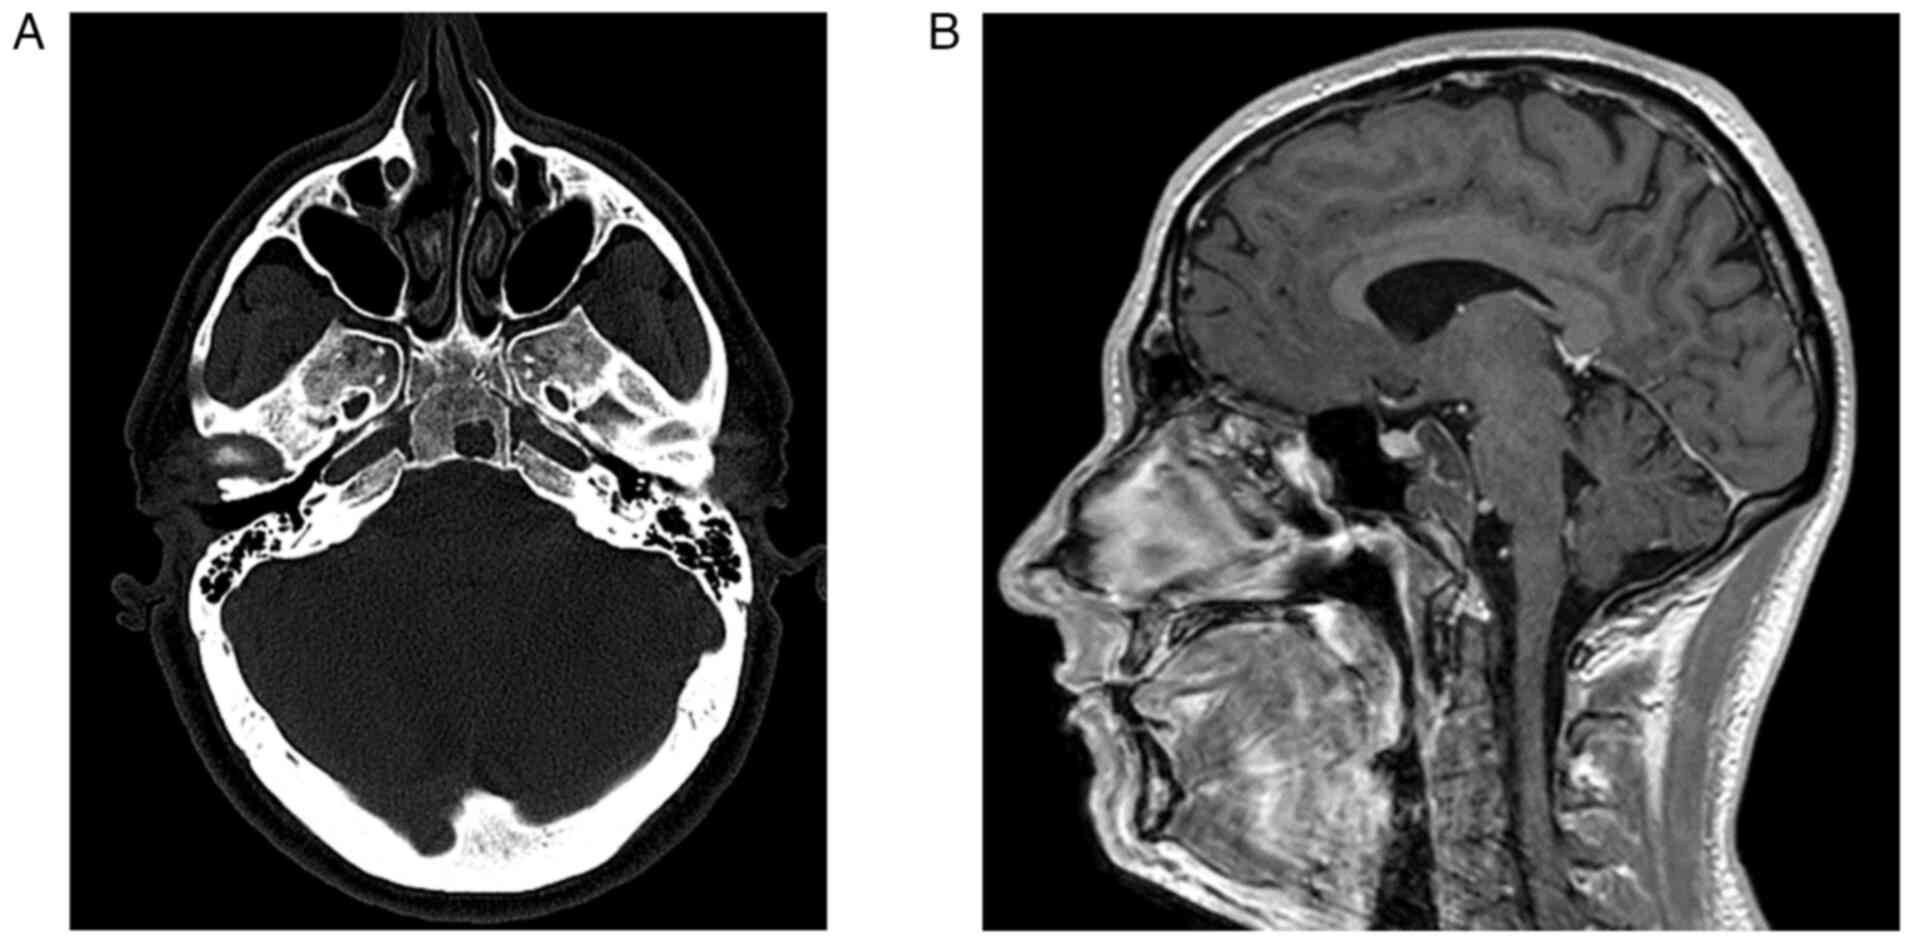

Lesions appeared as solid masses isointense to brain parenchyma in both standard T1 and T2-weighted images (Fig. 1A and B). Following contrast administration, a wide range of enhancement was observed, from non-enhancement in three cases, weak enhancement in three cases, to discrete enhancement in the last case. Calcifications were noted in two cases. In one case, the CH remained confined to the occipital bone, while in the remaining cases, it extended extradurally in all directions, including the cervical spine at the level of the extracanalar laterocervical area, the posterior cranial fossa, cavernous sinus, Meckel's cave, sphenoidal sinus, and intrasellar region, resulting in compression of the pituitary gland. The mean tumor size was 2,61 cm (range: 1,7-4 cm), with the mean neoplastic volume measured at 13,5 cm3 (range: 3–48 cm3). MRI findings were available for all cases. The follow-up period for patients ranged from one to 60 months, with a mean follow-up of 18.8 months. The associated disease, neurological status, and magnetic resonance features are described in Table I. Surgical treatment was performed via endonasal endoscopy in all cases, achieving complete removal of the clival CH in five cases. Radiotherapy was not administered in six cases, while three cases received stereotactic radiotherapy with a 30 Gy isodose delivered in five fractions, and one case underwent proton beam therapy at 74 Gy. During the follow-up period, no patients died from the disease; however, one patient was lost to follow-up, and there was no record of ongoing therapy. Another patient refused radiotherapy and experienced an increase in the residual lesion a few months postoperatively. Four patients experienced disease recurrence at one, nine, and 17 months, respectively.

Figure 1.

(A) Computed tomography scan with bone reconstruction algorithm showing a small non-enhancing bone lytic lesion with irregular borders at the level of the middle clivus. The lesion measured 1.7×1.5×1 cm and was centered in the right paramedian area. (B) Contrast-enhanced magnetic resonance study revealing a clival lesion with moderate enhancement, infiltrating and replacing the upper half of the clival cortical bone, extending widely toward the prepontine cistern. The lesion measures ~32×30×20 mm, infiltrates the dorsum sellae and shows close continuity with the pituitary gland, both carotid arteries, and the basilar trunk, reaching the sphenoid sinus.